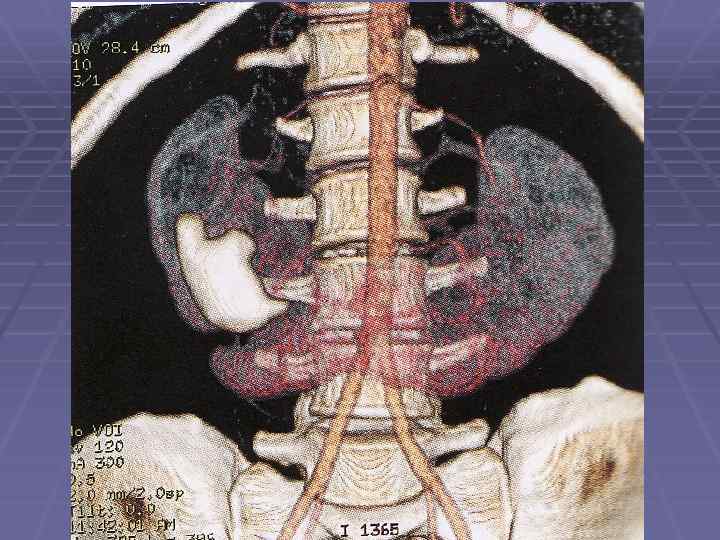

Мультиспиральная КТ почек Сосудистая фаза

Мультиспиральная КТ почек Экскреторная фаза